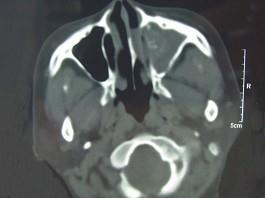

问题 男,41岁,左侧鼻腔胀痛半年余,CT检查如图,最可能诊断为 ( )

选项 A、真菌性鼻窦炎 B、上颌窦癌 C、化脓性鼻窦炎 D、变应性鼻窦炎 E、出血坏死性息肉

答案 A